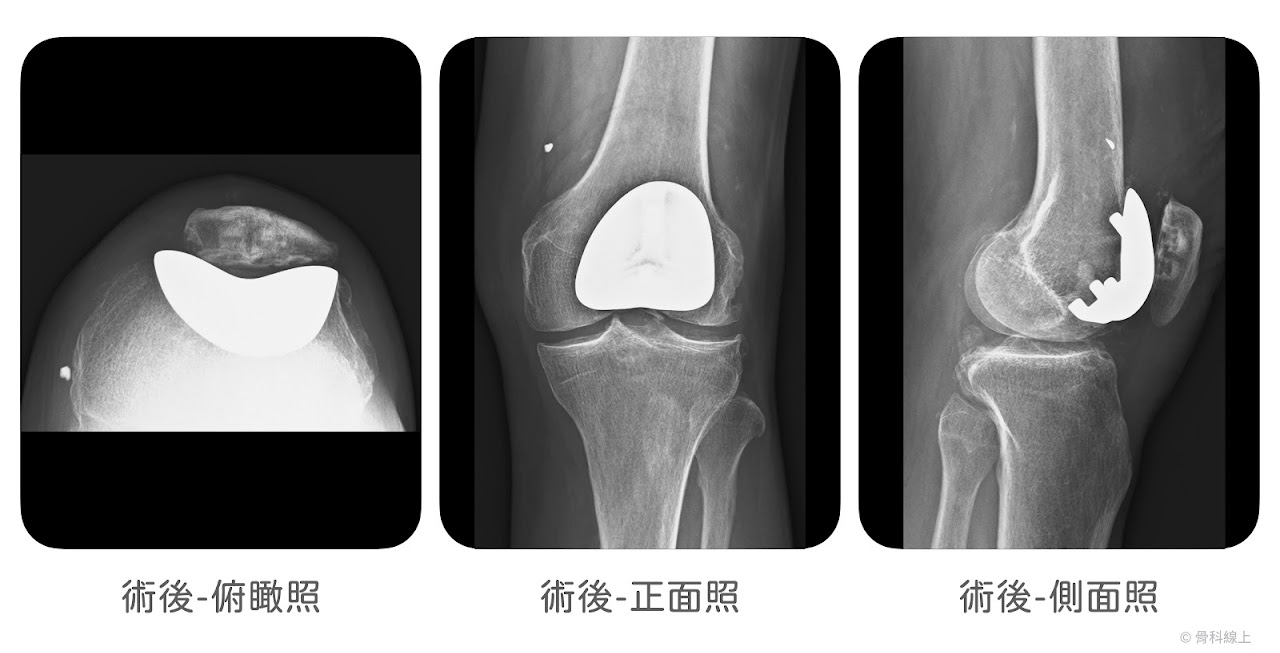

髕骨股骨人工關節置換手術

髕骨股骨人工關節,我們會說前方膝蓋骨的磨損,所以這樣的置換手術,不會處理內、外側關節面,也需符合幾個特定條件:

(1) 只有前方,髕骨股骨關節面的磨損

髕骨股骨關節面的磨損,常合併明顯的髕骨外翻或是脫位,所以髕骨股骨關節置換手術的概念,像是「重新鋪一個飛機跑道」讓髕骨可以穩穩的「降落」在軌道裡面,並且使表面光滑(resurfacing),緩解磨損症狀。

髕骨股骨人工膝關節置換手術過程示意圖